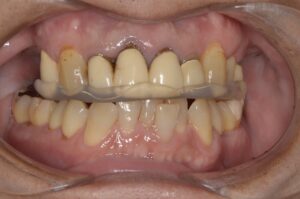

インプラントが入った状態で再度スプリントを入れて顎の位置の確認をしました

経過は端折りますが、初診時よりは良い位置に変わってきたものの、前方に転位した関節円板は戻すことができませんでした。

患者さんと相談の上、この位置で最終補綴に入りました。

最終補綴です。咬合平面も修正されています。